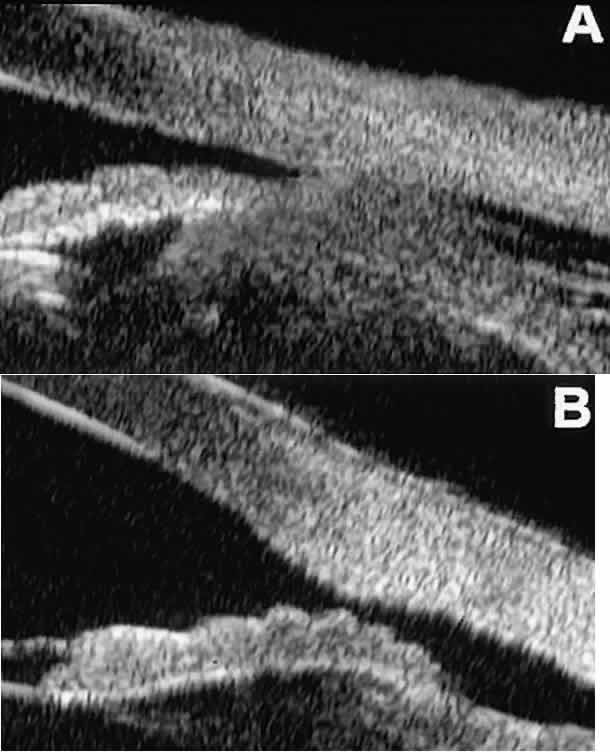

After any type of glaucoma filtering surgery,10 UBM can be used to detect and evaluate the extent of postoperative complications

such as ciliochoroidal effusion and cyclodialysis.3,4 In ciliochoroidal effusion (Fig. 13A), UBM shows the ciliary body to be edematous and separated from the sclera

by a sonolucent collection of supraciliary fluid. Many ciliochoroidal

effusions that are too limited in extent to be detectable by indirect

ophthalmoscopy and slit lamp biomicroscopy can be imaged by UBM. In

cyclodialysis (see Fig. 13B), UBM shows a well-defined separation between the uveal tissue and the

sclera in the region of the scleral spur. The width of the cleft is usually

assessed best by means of limbus-concentric images through the

region of interest.  Fig. 13. Complications of intraocular surgery. A. Postoperative ciliochoroidal effusion appears as slitlike spaces filled

with serous fluid posterior to scleral spur. B. Postoperative cyclodialysis appears as complete separation of iris and

ciliary body from sclera in region of scleral spur. Fig. 13. Complications of intraocular surgery. A. Postoperative ciliochoroidal effusion appears as slitlike spaces filled

with serous fluid posterior to scleral spur. B. Postoperative cyclodialysis appears as complete separation of iris and

ciliary body from sclera in region of scleral spur.

|